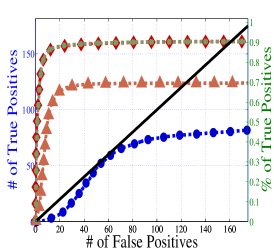

To understand the performance of this standard method, we present a small preview of our simulation study discussed later in Section 4. Briefly, we assume that each subject graph in group follows a small-world structure on nodes; in group , there are in addition 150 differential edges, meaning that and for all differential edges, . We generate data according to this model with time points and subjects in each group. Figure 1 illustrates the results of this standard approach as well as our new procedure, , which we will introduce later in Section 3. Part (a) gives ROC curves for the number of false positives verses true positives as each sequential test is rejected; parts (b) and (c) give the adjacency confusion matrix illustrating where the true and false positive as well as false negative edges are detected in the graph structure.

Our motivating simulation shows that the standard approach performs terribly in terms of both error control and statistical power. While the magnitude of the poor performance of this approach may seem astonishing, the poor performance should come as no surprise: The inferential procedure (e.g. test statistics) of the standard approach assume a one-level model that would be appropriate when the subject graphs are fixed and known or directly observed quantities. When these subject networks are unobserved, however, and must be estimated from finite data, these one-level test statistics are incorrect for our two-level problem. Specifically for two-level problems, the variance of parameters estimated by incorrectly assuming a one-level models is underestimated. For our problem, the extra source of variability arises from the graph selection procedure; we discuss challenges associated with this subsequently in Section 2.2. Incorrect variance estimates, however, are not the only problem with the standard approach: A more subtle problem arises from the fact that the proclivities of graph selection procedures for the Gaussian graphical model lead to biased estimates of the edge proportions, . As discussed in Section 2.3 and seen in Fig 1, graph selection false positives and false negatives do not occur at random throughout the network structure, leading to biased group level estimates.

Hence, the first term represents variability across subjects in group and the second term represents the variability associated with the selection procedure within subject , a quantity that we assume to be constant across subjects in each group . Consider now what happens if our true model follows this two-level Beta-Binomial model, but as with the standard approach, we use a one-level Binomial model and associated two-sample test statistic. The variance is thus underestimated and the test statistic is overoptimistic. Then, when inference is conducted for the population mean , using the incorrect Binomial model leads to inflated Type I error rates; this behavior has been well-documented (Weil, 1970; Liang and Hanfelt, 1994). Hence, failure to use the correct two-level model which accounts for the two levels of network variability partially explains the high error rates of the standard procedure observed in Figure 1.

In Figure 4 and Table 1, we present our main simulation results comparing to the two variations of our method and the standard approach for three network structures and Case I and II type differential edges. First for Figure 4, we report results in terms of operating characteristics averaged across 50 replicates with the number of true positives (y-axis) plotted against the number of false positives (x-axis) for each test statistic, rejected sequentially from largest to smallest in absolute magnitude. Overall, all of our methods and particularly yield substantial improvements over the standard approach in all scenarios.